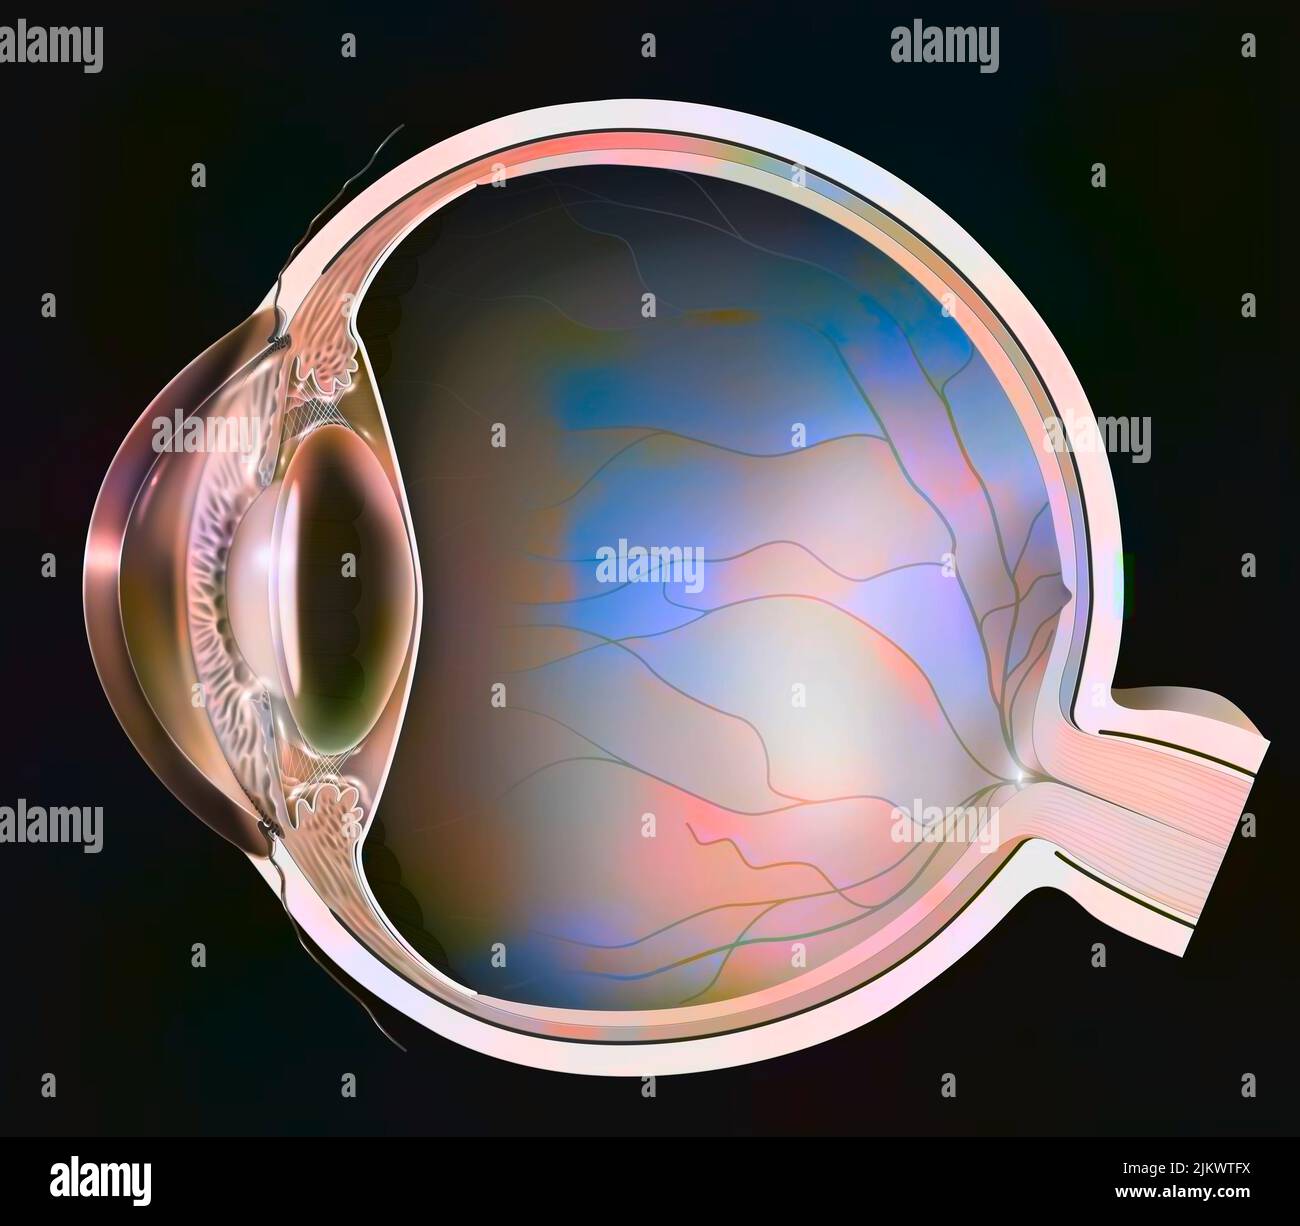

RF2JKWT9A–Oeil, cataracte, phacoémulsification - étape 2: Consiste à casser la lentille avec une sonde.